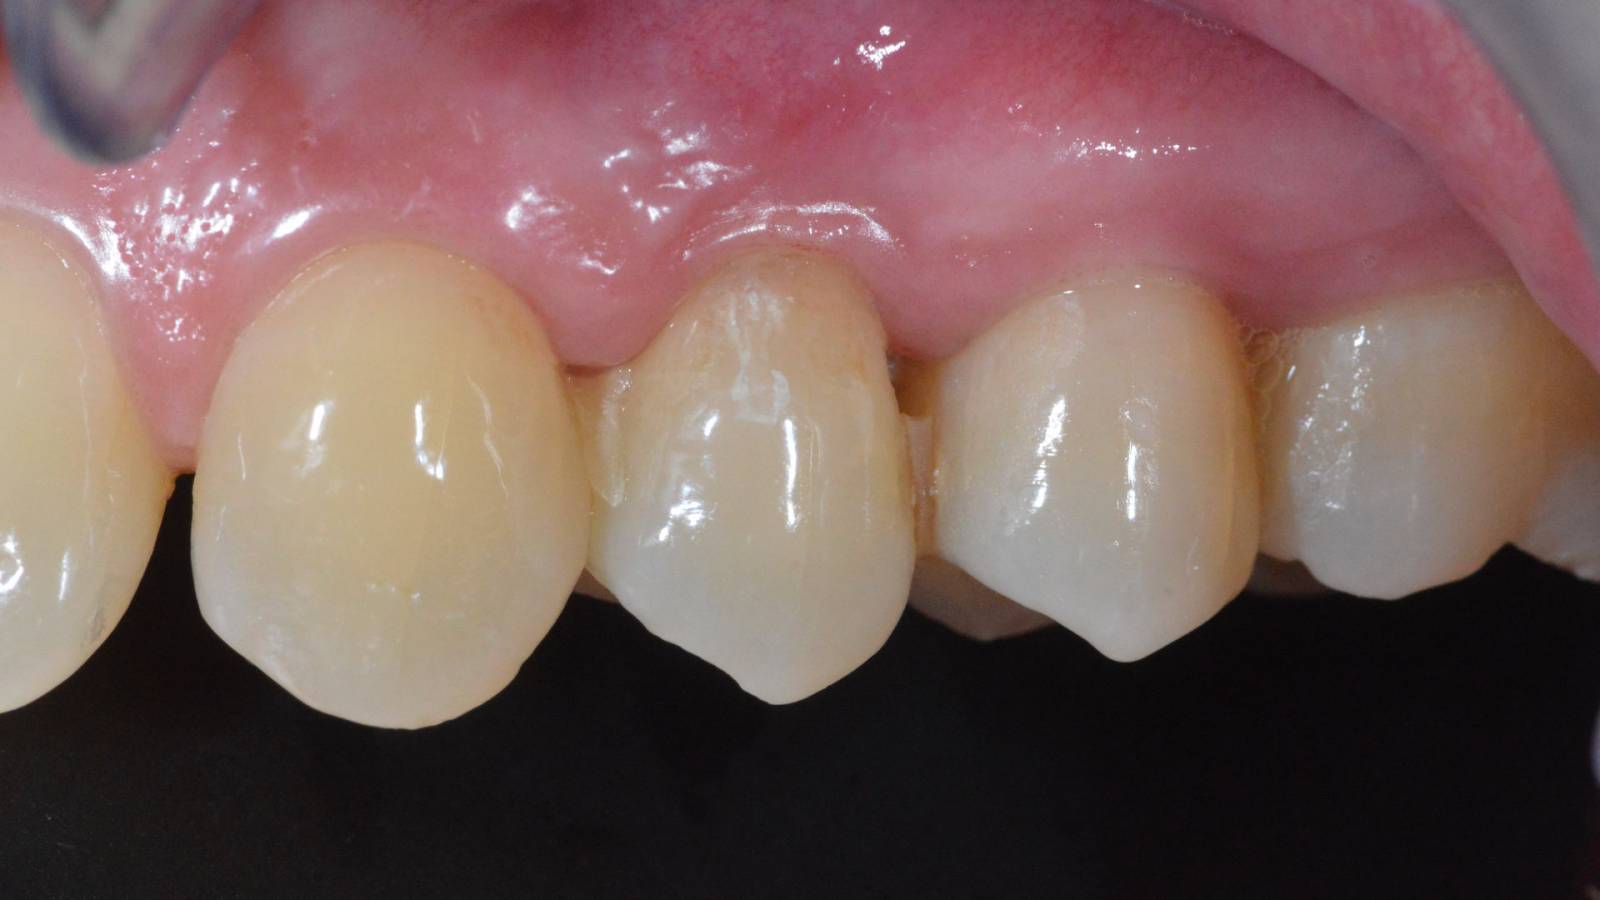

Upper central incisors, in 4 hours

Four IPS e.max CAD single crowns

The restoration with all-ceramic crowns did not require subgingival preparation to cover the margin and no dark metal shadows disturbed the esthetics. With CEREC Primescan and CEREC Primemill patients receive a high-quality all-ceramic restoration faster than ever before.

Before: Inadequate fillings on teeth 12-22, an uneven gingival line on 12 and 11 and incisal edges severely eroded.

After: Four highly esthetic and individualized lithium disilicate ceramic crowns.